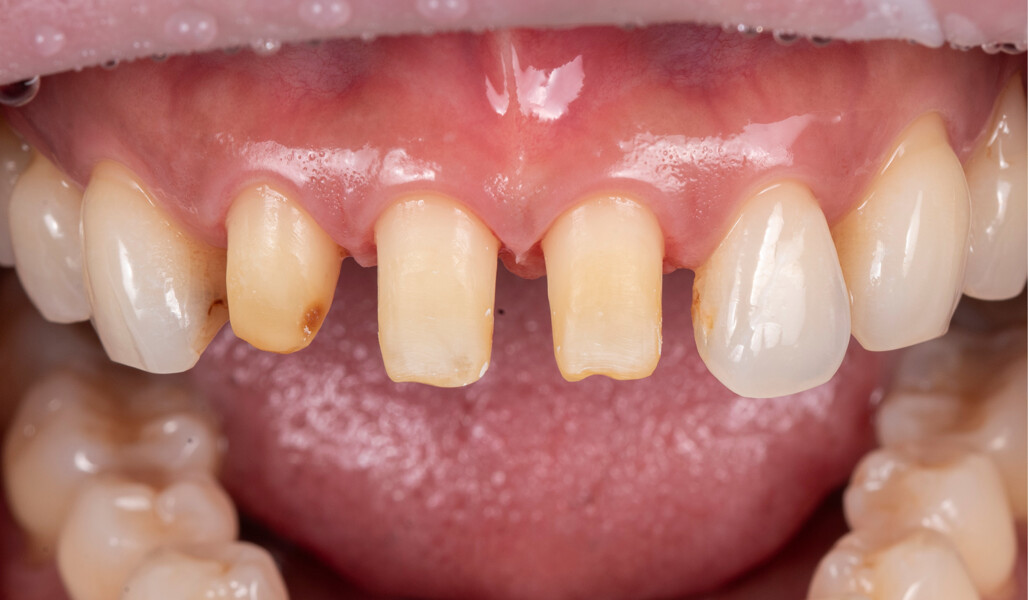

In this article, this point is demonstrated based on the case of a middle-aged female patient who presented with very unsatisfactory metal–ceramic crowns and asked for an aesthetic improvement of the situation (Fig. 1). The crowns on her maxillary central incisors and right lateral incisor clearly needed to be replaced not only for aesthetic reasons but also for functional ones. As anterior interferences were present and orthodontic treatment was not an option, the decision was made to select a ceramic material with a particularly high strength—KATANA Zirconia HT (Kuraray Noritake Dental)—and to opt for a design that would support the incisal edge with zirconia. Consequently, porcelain layering with CERABIEN ZR (Kuraray Noritake Dental) would be limited to the vestibular region (Figs. 2–11).